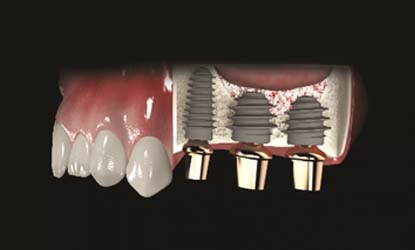

Problema: Trūksta visų dantų

Tikslas:

Pakeisti trūkstamus dantis dantų implantais

Rezultatas:

Atkurta pilnavertė kramtymo ir estetinė funkcija fiksuotais dantų protezais